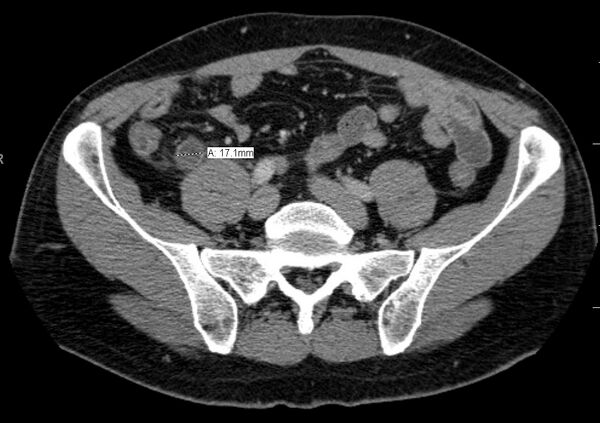

- Экспериментальные данные свидетельствуют о том, что острый аппендицит, по-видимому, возникает в результате обтурации (закупоривания) просвета червеобразного отростка[7][8]. Обтурация приводит к переполнению просвета отростка дистальнее уровня обтурации слизистым секретом. Диаметр отростка возрастает с 4-6 мм в норме до 17-18 и более миллиметров, он становится напряжённым. Нарастающее внутрипросветное давление в течение нескольких часов приводит к сдавлению внутриорганных вен, нарушению венозного и лимфатического оттока, отёку стенки органа и пропотеванию транссудата в его просвет с дальнейшим увеличением внутрипросветного давления («порочный круг»), что приводит к острому воспалению и некрозу (омертвению), прежде всего в зоне давления инородного тела («декубитальная язва», «пролежень», «флегмонозно-язвенный аппендицит»). Иногда копролиты можно обнаружить в просвете червеобразного отростка при остром катаральном или хроническом аппендиците. Почему они не приводят к деструкции органа и как долго находятся в его просвете, пока не ясно.

Ультразвуковое исследование — дилятация просвета (диаметр более 6 мм), отсутствие перистальтики, иногда может лоцироваться копролит. Ультразвуковое исследование должно быть первым инструментальным обследованием при подозрении на аппендицит. Обнаруживаются наполненная жидкостью, несжимаемая трубчатая конструкция с диаметром, превышающим 6 мм, аппендиколит, околоаппендикулярная перицекальная жидкость.

Компьютерная томография информативна при наличии спирального томографа, когда выявляется обтурация червеобразного отростка, расширение его просвета, утолщение стенки (> 1 мм), признаки свободной жидкости (воспалительного выпота) в брюшной полости.